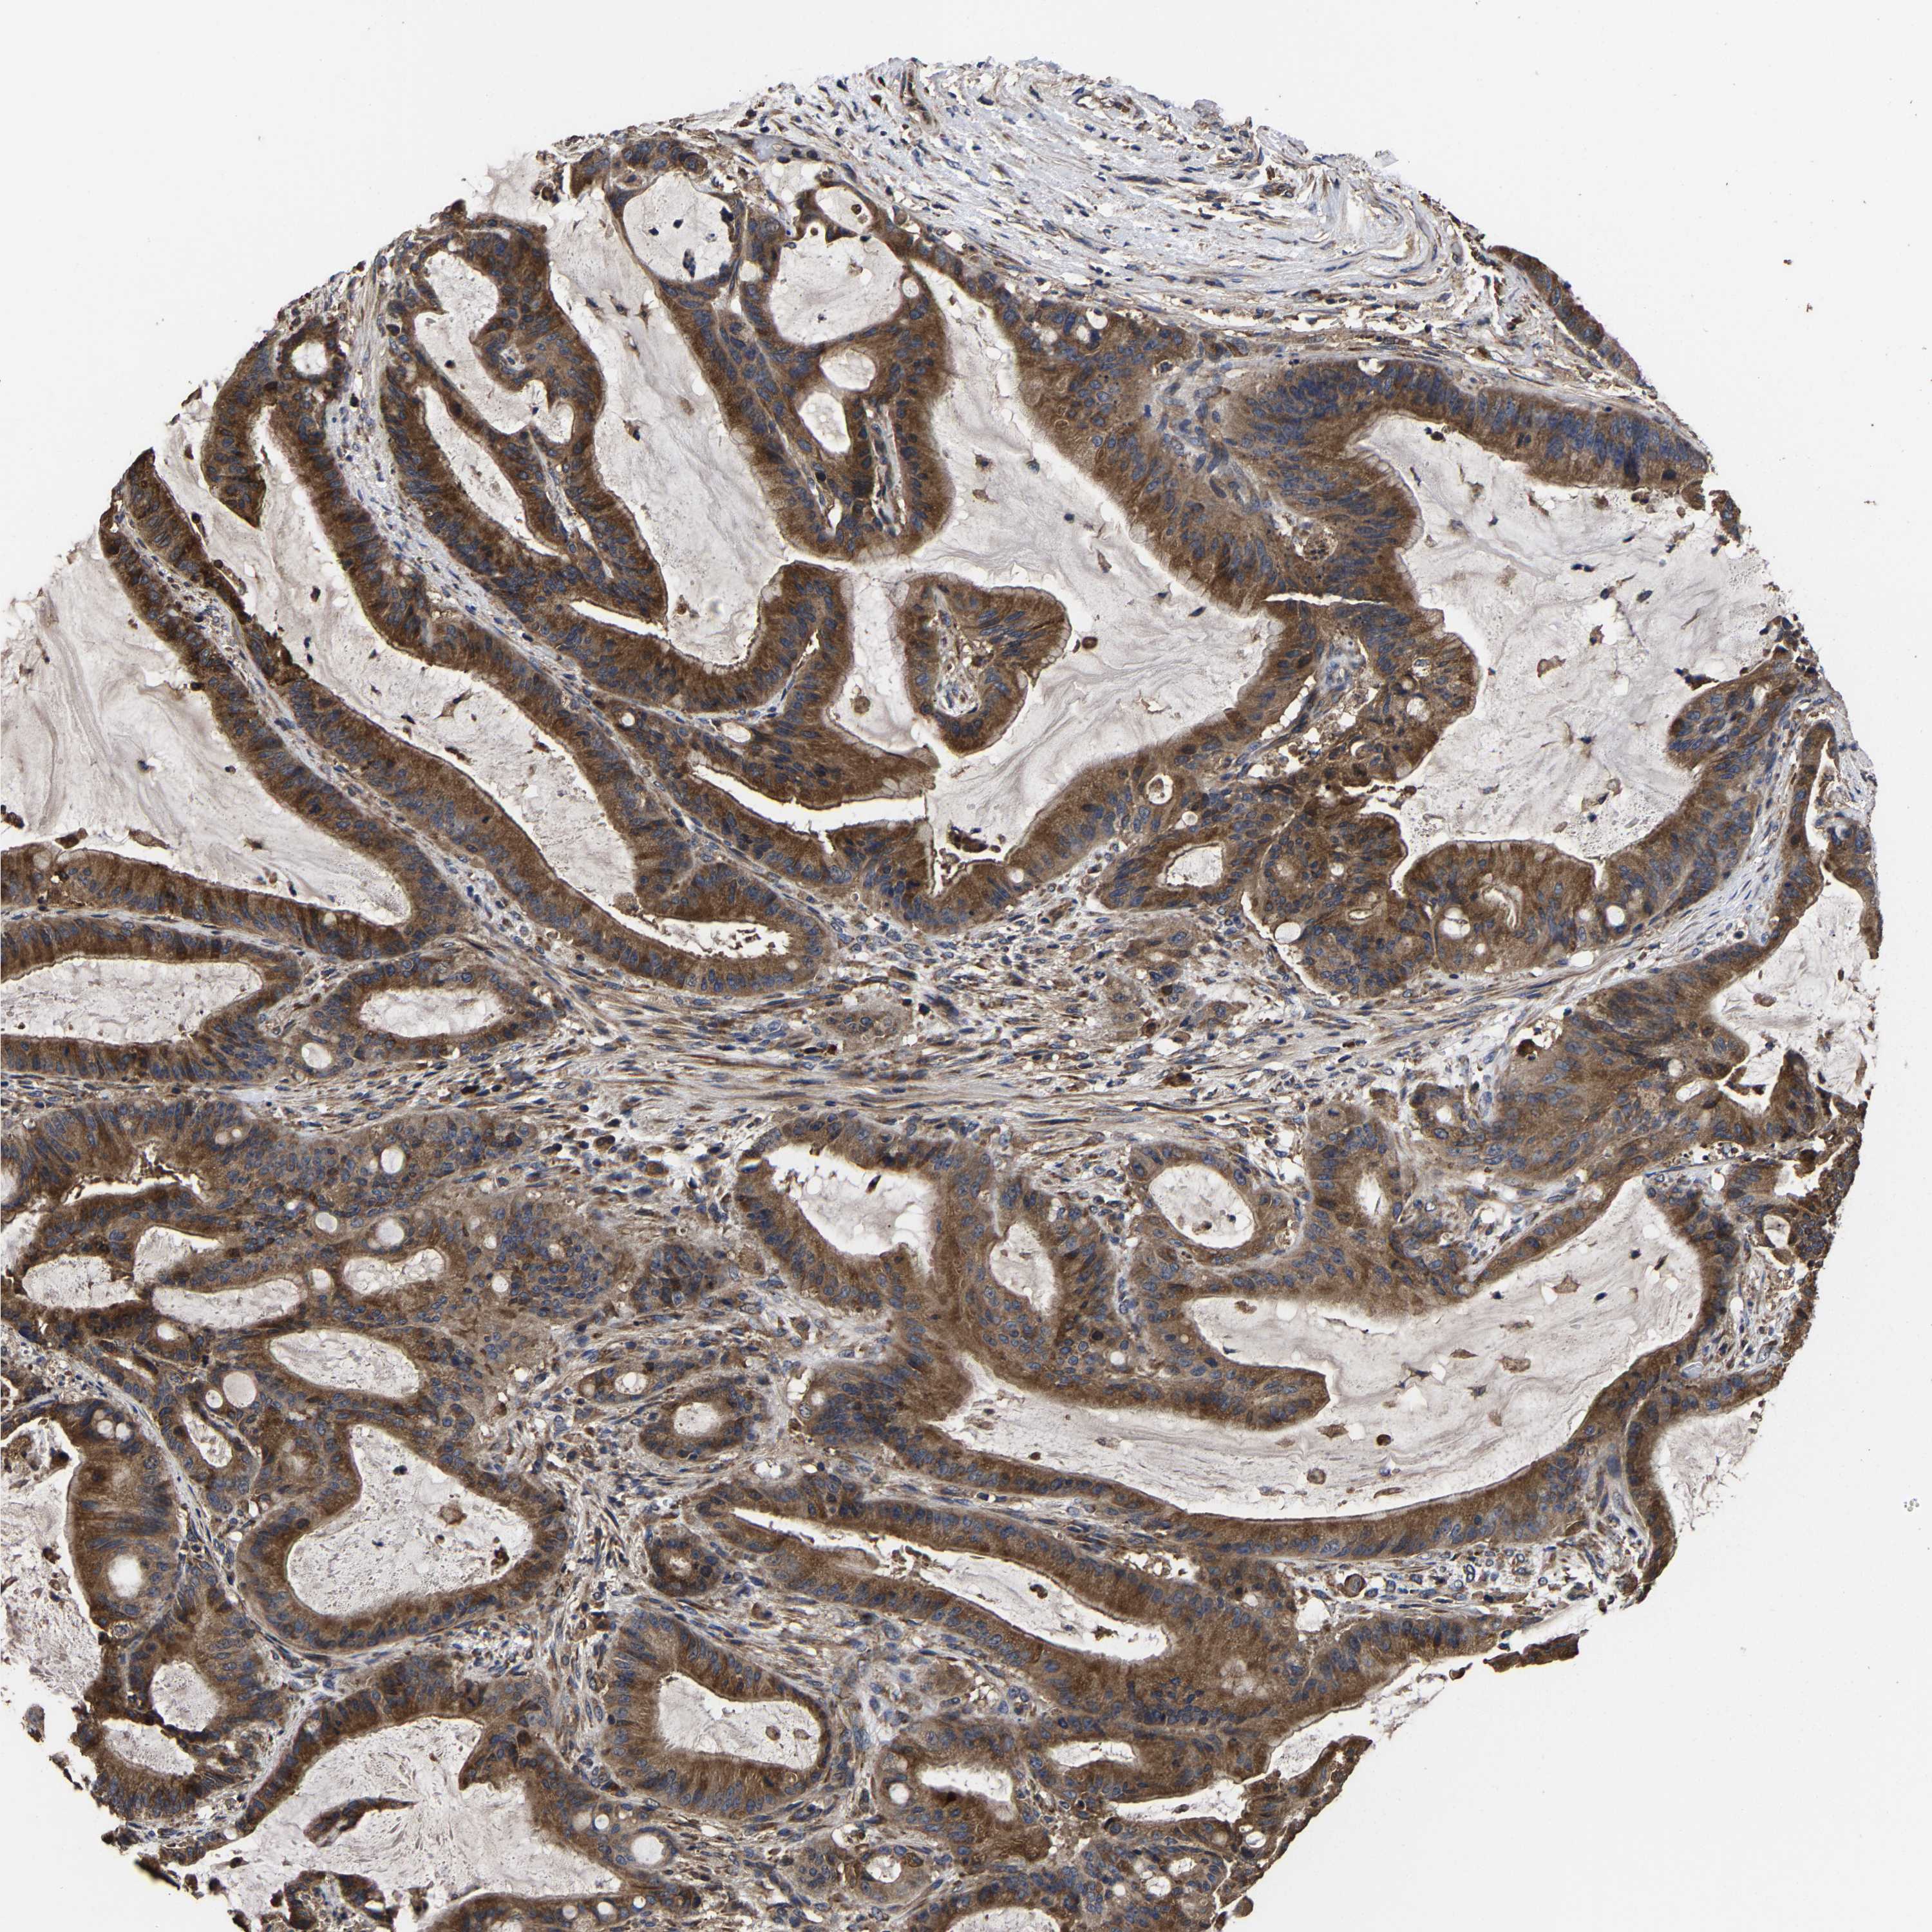

LIVER CANCER